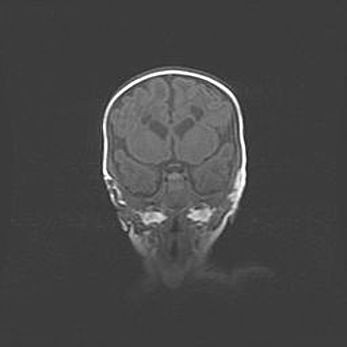

Церебральная ишемия II.

Возраст: 5 дней

Вес: 3400 г

Пол: женский

Окружность головы: 35 см

Срок гестации: 39 недель

Церебральная ишемия – это заболевание, характеризующееся недостаточностью (гипоксией) либо полным прекращением (аноксией) снабжения мозга кислородом по причине закупорки одного или нескольких сосудов. Это приводит к  что метаболическим расстройствам различной степени тяжести в тканях головного мозга, развитию коагуляционных некрозов и гибели нейронов.